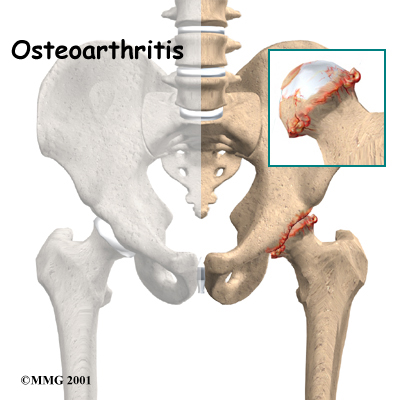

Articular cartilage is the smooth lining that covers the surfaces of the ball-and-socket joint of the hip. The cartilage gives the joint freedom of movement by decreasing friction. The layer of bone just below the articular cartilage is called subchondral bone. The main problem in OA is degeneration of the articular cartilage.

When the , or wears away, the subchondral bone is uncovered and rubs against bone. Small outgrowths called bone spurs or osteophytes may form in the joint.